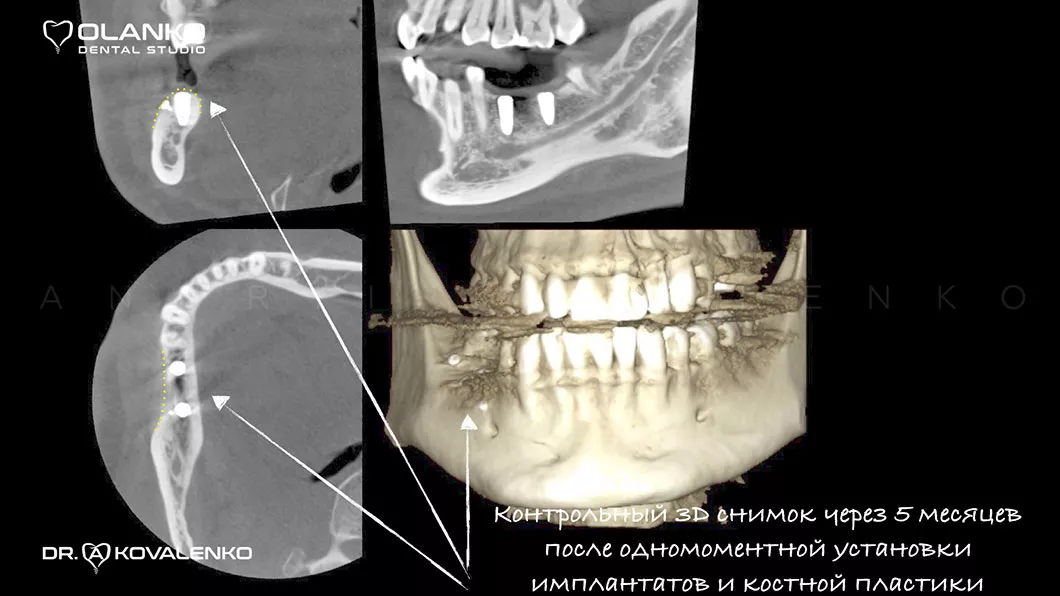

Вигляд кістки після кісткової пластики та встановлення зубних імплантатів

Вигляд кістки після кісткової пластики та встановлення зубних імплантатів Оланко Бровари Київ